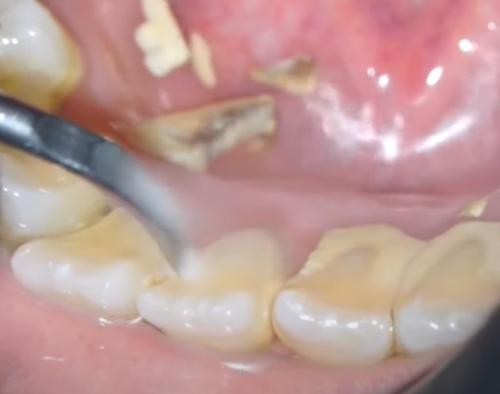

치석 축적은 충치 와 잇몸 후퇴를 직접적으로 유발합니다.

충치는 치아 법랑질 에 대한 영구적인 손상입니다. 충치는 치료하지 않고 방치하면 치아를 상실해야 함을 의미할 수 있습니다. 드물게 잇몸 질환이 치명적일 수도 있습니다.

치아에 치석이 보인다면 박테리아가 끊임없이 법랑질을 먹고 있다는 뜻입니다. 그리고 당신은 그것을 닦거나 긁어낼 수 없습니다. 이는 치석이 제거될 때까지 손상이 계속 발생한다는 것을 의미합니다.